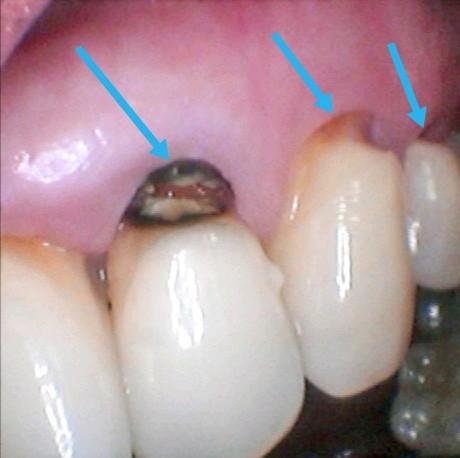

第五类是发生在牙齿的唇侧或者是舌侧的将近牙龈1/3颈部的龋齿所制备的洞,叫做Ⅴ类洞。(图十一)箭头指向

图十一

处理方案:1、补牙

2、全瓷贴面

分析:牙齿颈部龋坏首选是补牙,前提先要改变刷牙的方法和矫正咬紧牙或夜磨牙的的习惯,防止补牙材料受外力作用脱落。(图十二)。

如果龋坏缺损面积过大补牙后影响美观建议做全瓷贴面。